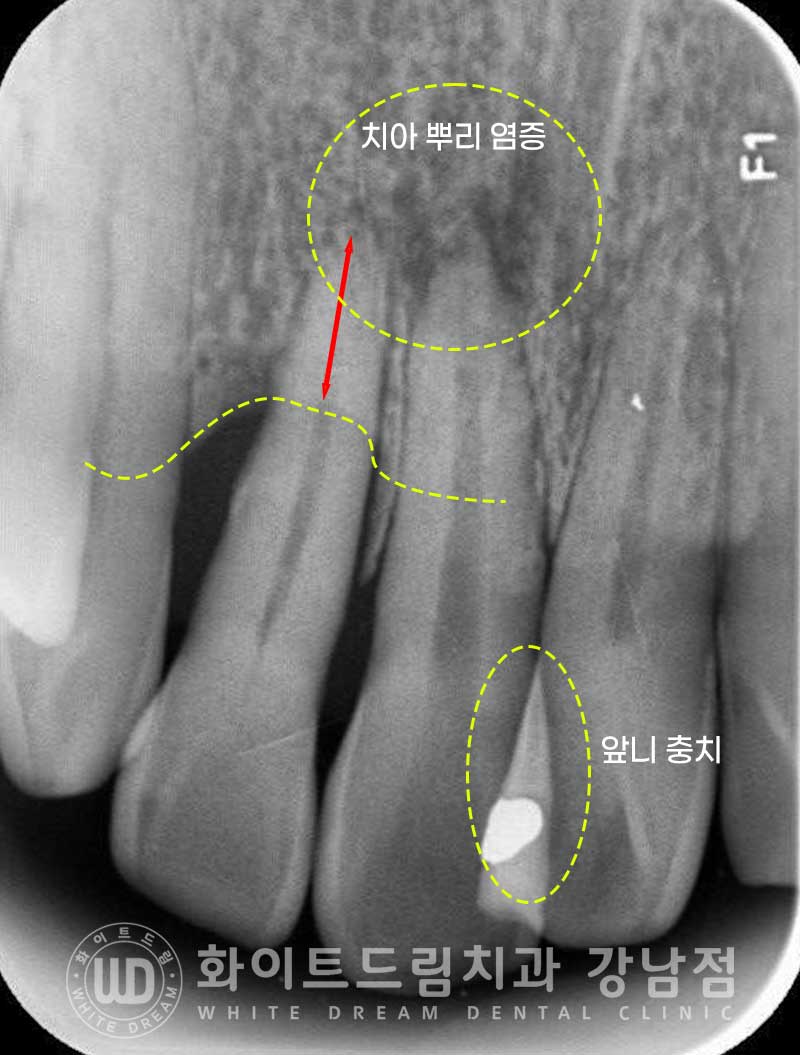

치아의 상태를 보다 정확하게 확인하기 위해 치근단 사진을 촬영해 봤습니다.

12번 치아의 치주 인대가 손상되어 염증이 발생했고

이로 인해 주위 잇몸뼈가 녹기 시작한 것으로 추측되었습니다.

또한 11번 변색된 치아 끝 부위에 치아 뿌리 염증이 자리를 잡고 있는 것이 확인됩니다.

아마 외상을 당하셨을 때 치수가 손상되었고 천천히 괴사가 일어나

치아 뿌리에 염증이 발생한 것으로 추측되었습니다.

이 치아 뿌리 염증과 인접면 충치 치료를 진행하기 위해

11번, 21번 치아는 신경치료를 진행하기로 하였고

잇몸뼈가 심하게 녹아 흔들림이 심한 12번 치아는 발치 후 임플란트를 식립하기로

환자분과 상의 후 결정되었습니다.